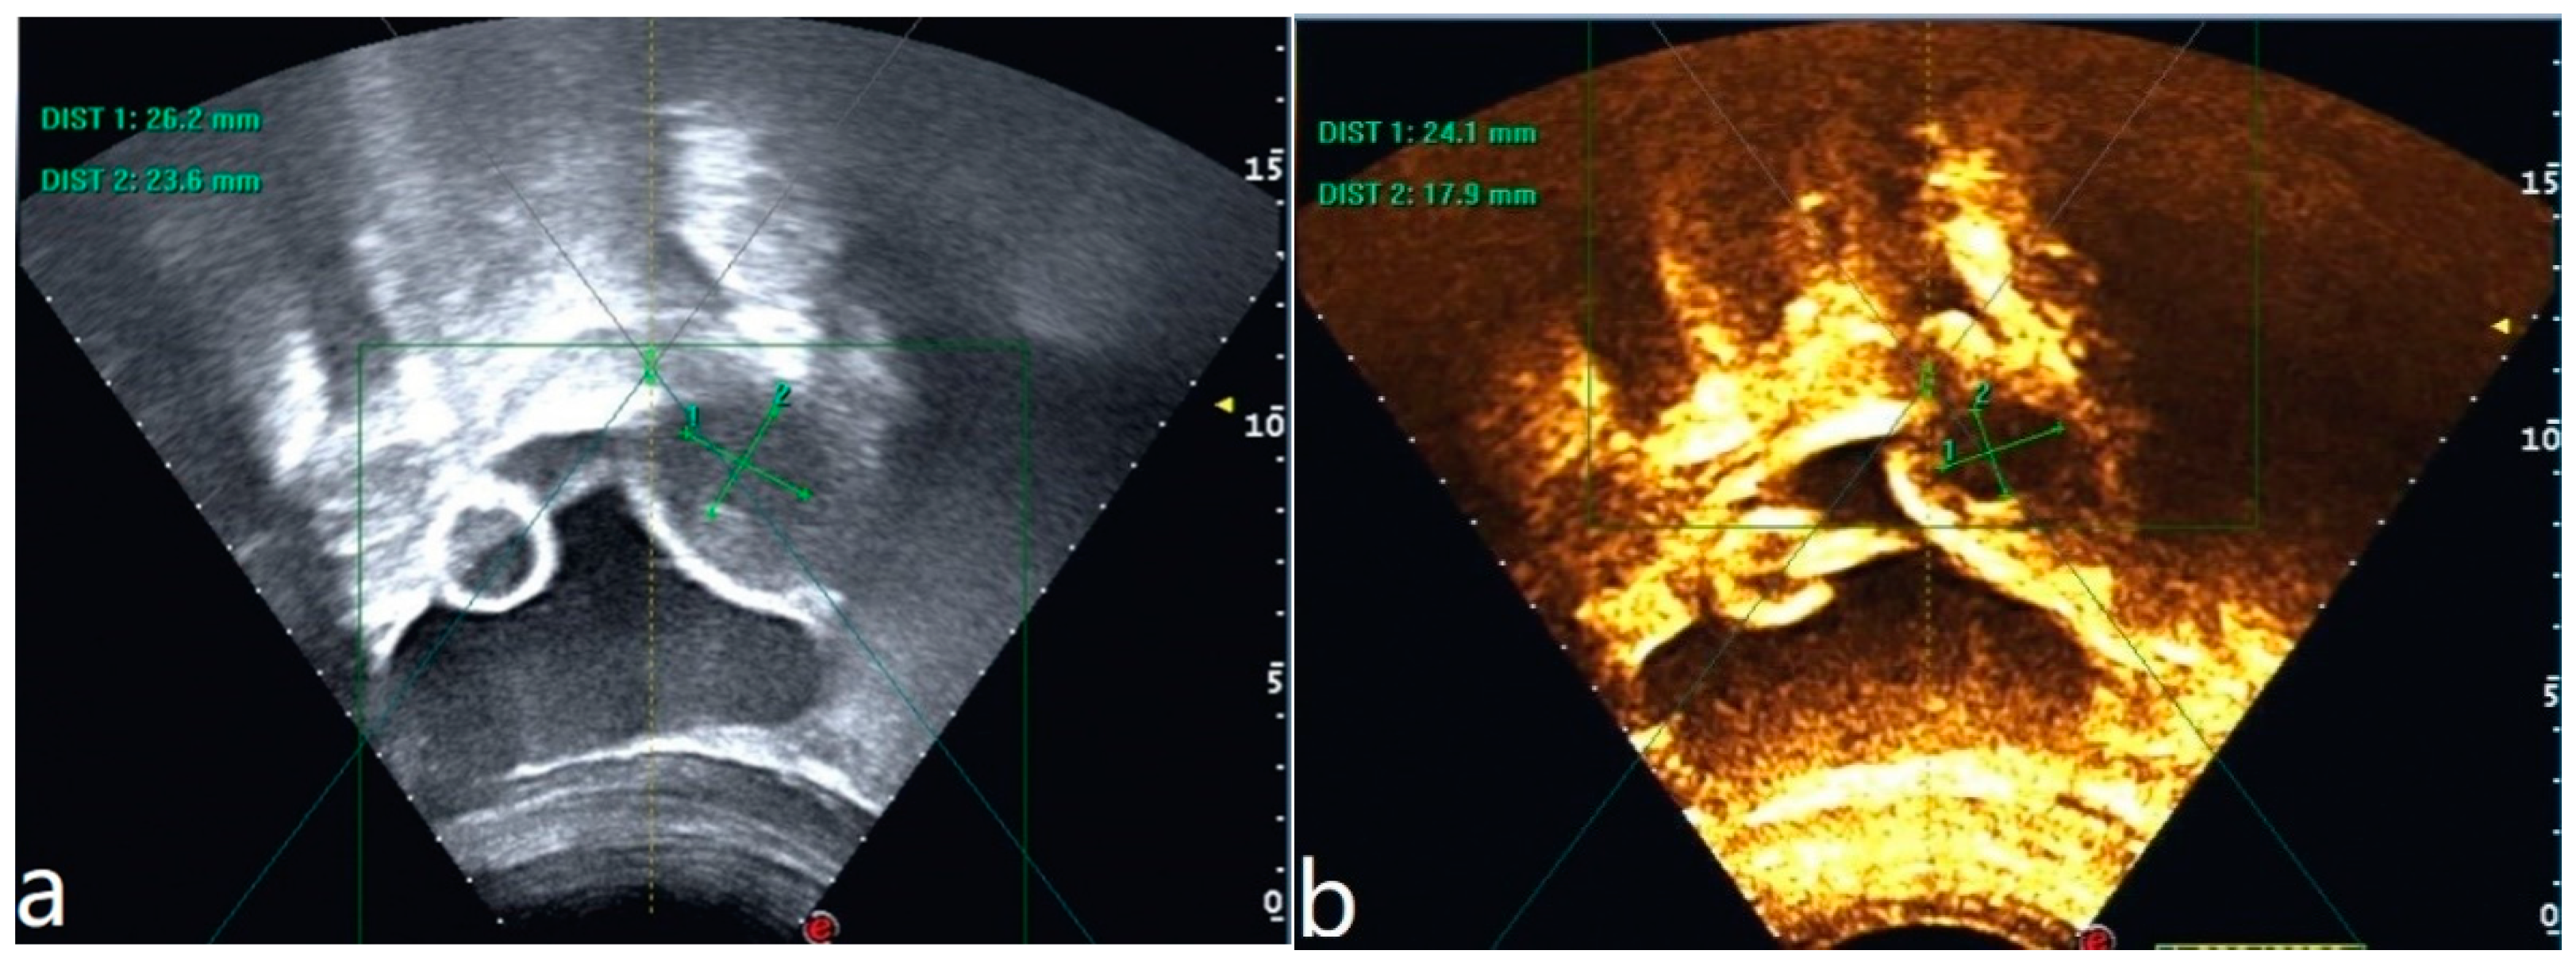

Figure 1.

(a–c) Pelvic MRI: sagittal TIWI sequence (a), sagittal T2WI fat suppression sequence (b), and axial T2WI non-fat suppression (c) showing a cystic lesion in the right posterior wall of the uterus with regular morphology, oval shape, and clear border (red arrows).